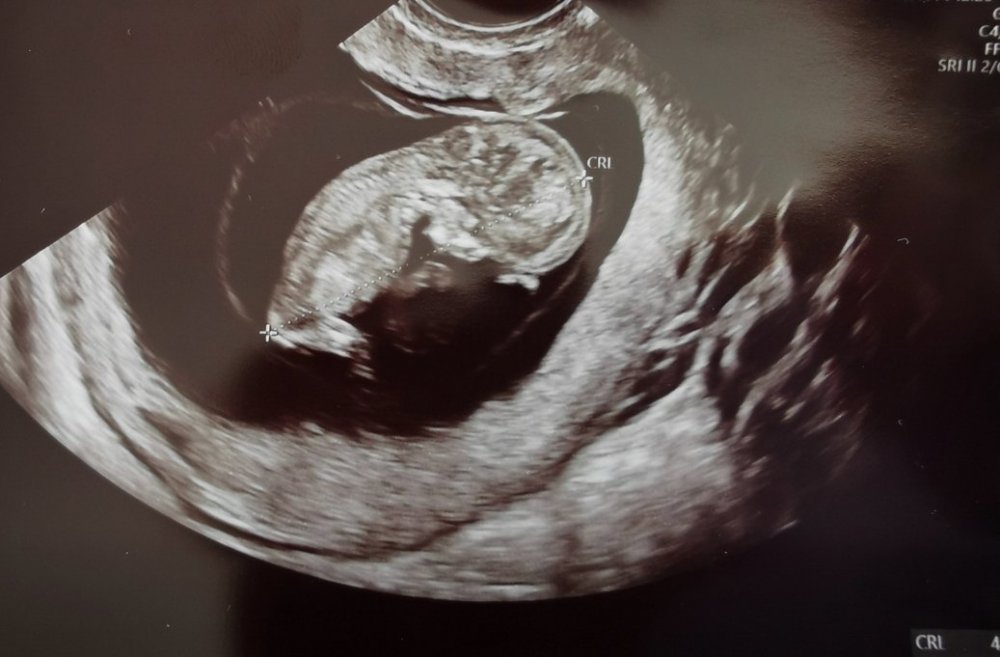

Byłam na wizycie u mojej gin.

Maleństwo pięknie rośnie, serduszko bije równo. Na liczniku mamy dzień do przodu czyli 13+1. Karotka podskakiwała i się ruszał że hej, nie dała się dobrze podejrzeć 😉

Jak mnie ta wizyta uspokoiła🙂

We środę prenatalne,ale wiem że będzie dobrze.